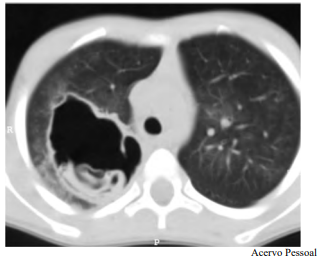

A doença apresentada é diagnosticada facilmente em pacientes com lesões císticas pulmonares e teste sorológico positivo, que moram em zonas endêmicas, como o paciente do caso clínico.

O órgão acometido pela doença infecciosa do paciente é o sítio preferencial de acometimento por esse germe, e o segundo órgão preferencial é o fígado.